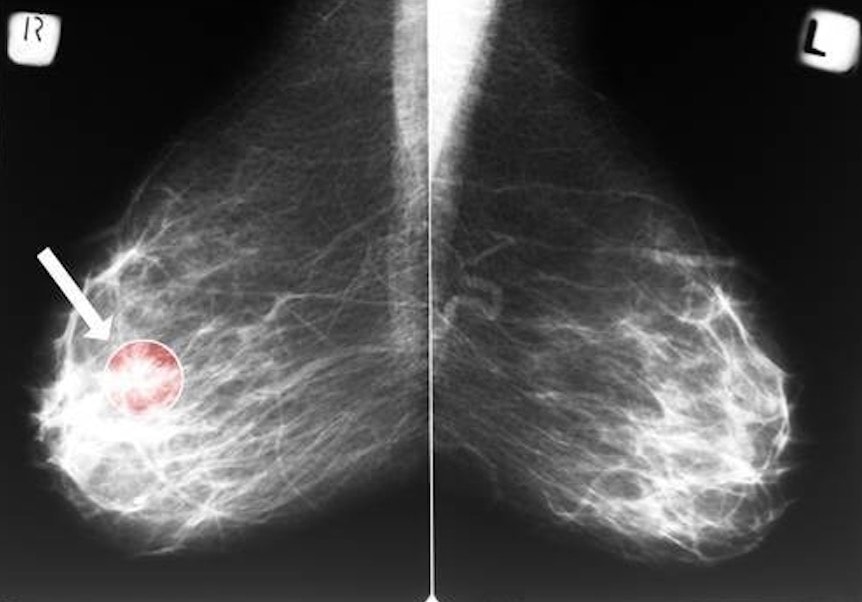

Rak piersi to najpowszechniejszy typ nowotworu u kobiet na całym świecie. World Cancer Research Fund International tylko w 2012 roku ogłosił aż 1,7 milionów nowych przypadków zachorowań. Około połowa ze zdiagnozowanych na całym świecie kobiet posiada status HER2 ujemny. Jest to receptor kluczowy w tworzeniu się komórek nowotworowych. Taką odmianę nowotworu leczy się między innymi lekami blokującymi estrogen oraz różnymi dawkami chemioterapii.

Wyniki badań dają nadzieję kobietom z ujemnym statusem HER2 i wczesnym stadium guza (poniżej 5 centymetrów) oraz brakiem przerzutów do węzłów chłonnych. Pacjentki miały także wynik testu Oncotype DX między 11 i 25 punktów.